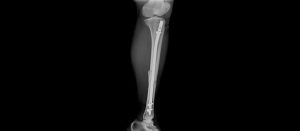

Hình ảnh chụp X-quang xương cẳng chân của bệnh nhân trước và sau phẫu thuật

Sau 1 giờ phẫu thuật dưới hướng dẫn của hệ thống C-arm, kết quả kiểm tra phim chụp X-quang 2 xương cẳng chân của bệnh nhân cho thấy xương nắn chỉnh tốt. Sau mổ 1 ngày bệnh nhân đã giảm đau rõ rệt và đã có thể tập vận động. Sau phẫu thuật 7 ngày, tình hình sức khỏe của bệnh nhân hồi phục tốt và đã được ra viện vào ngày 02/10/2023.